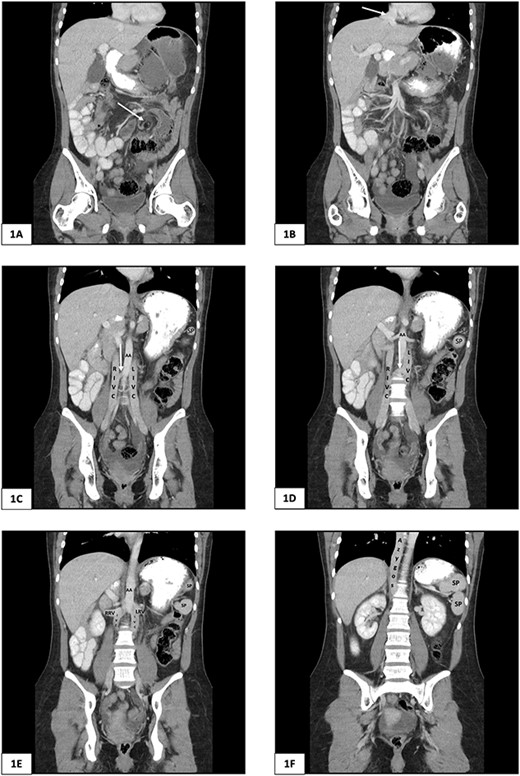

A plain abdominal X-ray was performed showing a grossly distended loop of colon in the left upper abdomen. Subsequent computed tomography (CT) scan of the abdomen and pelvis was obtained using oral and intravenous contrast with images acquired during portal venous phase. The CT showed a mesenteric whirl sign (Fig. 1A) and caecal volvulus with the caecum measuring 97 mm diameter at its most distended point with associated pneumatosis coli (Fig. 2A and B).

Computed tomography of the abdomen and pelvis of 25-year-old female presenting with caecal volvulus, intestinal malrotation, duplicate inferior vena cava, azygos continuation of the IVC, and fragmentation of the spleen. RIVC, right inferior vena cava; LIVC, left inferior vena cava; RRV, right renal vein; LRV, left renal vein; AA, abdominal aorta; SP, splenic fragment. (A) Arrow indicates mesenteric whirl sign. (B) Arrow indicates suprahepatic IVC draining from right, middle, and left hepatic veins into the right atrium. (C) and (D) Arrow indicates communicating vein from right IVC to left IVC.

There was malrotation of the gut with all colon on the left side and most of the small bowel on the right side of the abdomen (Fig. 2A). There was duplication of the infrarenal IVC, interruption of the suprarenal IVC with azygos continuation (Fig. 1C–F). A left-sided IVC draining venous blood from the left common iliac vein was present which drained into the left renal vein, while the right IVC drained blood from the right common iliac vein into the right renal vein. A retroaortic communication draining blood from the right IVC into the left IVC was also noted. From the renal veins all venous return was via the azygos vein to the superior vena cava with interruption of the suprarenal IVC. A suprahepatic IVC draining blood from the middle, left, and right hepatic veins into the right atrium was present (Fig. 1B). The spleen was divided into five distinct fragments, all within the splenic fossa and each supplied by an individual branch of the splenic artery (Figs 1 and 2).